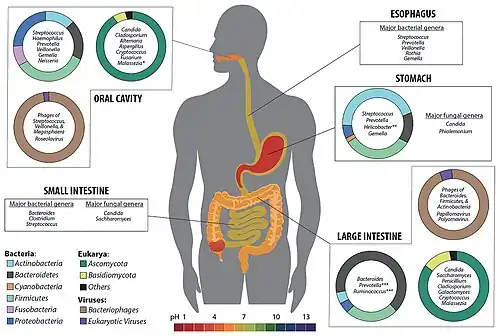

Gut microbiota, gut microbiome, or gut flora are the microorganisms, including bacteria, archaea, fungi, and viruses, that live in the digestive tracts of animals.[1][2] The gastrointestinal metagenome is the aggregate of all the genomes of the gut microbiota.[3][4] The gut is the main location of the human microbiome.[5] The gut microbiota has broad impacts, including effects on colonization, resistance to pathogens, maintaining the intestinal epithelium, metabolizing dietary and pharmaceutical compounds, controlling immune function, and even behavior through the gut–brain axis.[4]

The microbial composition of the gut microbiota varies across regions of the digestive tract. The colon contains the highest microbial density of any human-associated microbial community studied so far, representing between 300 and 1000 different species.[6] Bacteria are the largest and to date, best studied component and 99% of gut bacteria come from about 30 or 40 species.[7] About 55% of the dry mass of feces is bacteria.[8] Over 99% of the bacteria in the gut are anaerobes, but in the cecum, aerobic bacteria reach high densities.[5] It is estimated that the human gut microbiota has around a hundred times as many genes as there are in the human genome.

The microbial composition of the gut microbiota varies across the digestive tract. In the stomach and small intestine, relatively few species of bacteria are generally present.[6][18] Fungi, protists, archaea, and viruses are also present in the gut flora, but less is known about their activities.[19]

The four dominant bacterial phyla in the human gut are Bacillota (Firmicutes), Bacteroidota, Actinomycetota, and Pseudomonadota.[23] Most bacteria belong to the genera Bacteroides, Clostridium, Faecalibacterium,[6][7] Eubacterium, Ruminococcus, Peptococcus, Peptostreptococcus, and Bifidobacterium.[6][7] Other genera, such as Escherichia and Lactobacillus, are present to a lesser extent.[6] Species from the genus Bacteroides alone constitute about 30% of all bacteria in the gut, suggesting that this genus is especially important in the functioning of the host.[18]

Fungal genera that have been detected in the gut include Candida, Saccharomyces, Aspergillus, Penicillium, Rhodotorula, Trametes, Pleospora, Sclerotinia, Bullera, and Galactomyces, among others.[24][25] Rhodotorula is most frequently found in individuals with inflammatory bowel disease while Candida is most frequently found in individuals with hepatitis B cirrhosis and chronic hepatitis B.[24]

Due to the high acidity of the stomach, most microorganisms cannot survive there. The main bacteria of the gastric microbiota belong to five major phyla: Firmicutes, Bacteroidetes, Actinobacteria, Fusobacteriota, and Proteobacteria. The dominant genera are Prevotella, Streptococcus, Veillonella, Rothia, and Haemophilus.[31] The interaction between the pre-existing gastric microbiota with the introduction of H. pylori may influence disease progression.[31] When there is a presence of H. pylori it becomes the dominant species of the microbiota.[32]

The small intestine contains a trace amount of microorganisms due to the proximity and influence of the stomach. Gram-positive cocci and rod-shaped bacteria are the predominant microorganisms found in the small intestine.[5] However, in the distal portion of the small intestine alkaline conditions support gram-negative bacteria of the Enterobacteriaceae.[5] The bacterial flora of the small intestine aid in a wide range of intestinal functions. The bacterial flora provide regulatory signals that enable the development and utility of the gut. Overgrowth of bacteria in the small intestine can lead to intestinal failure.[34] In addition the large intestine contains the largest bacterial ecosystem in the human body.[5] About 99% of the large intestine and feces flora are made up of obligate anaerobes such as Bacteroides and Bifidobacterium.[35] Factors that disrupt the microorganism population of the large intestine include antibiotics, stress, and parasites.[5]

Five phyla dominate the intestinal microbiota: Bacteroidota, Bacillota (Firmicutes), Actinomycetota, Pseudomonadota, and Verrucomicrobiota – with Bacteroidota and Bacillota constituting 90% of the composition.[37] Somewhere between 300[6] and 1000 different species live in the gut,[18] with most estimates at about 500.[38][39] However, it is probable that 99% of the bacteria come from about 30 or 40 species, with Faecalibacterium prausnitzii (phylum firmicutes) being the most common species in healthy adults.[7][40]